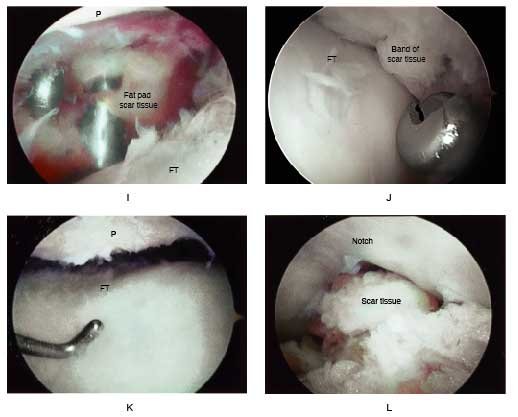

I, A view through the superolateral portal shows the fat pad and instruments to remove infrapatellar scar tissue. Care is taken to not transect the anterior medial and lateral meniscus attachments.

J, Extensive synovium and scar is removed from the medial and lateral recesses and intercondylar notch. There may exist scar tissue proliferation on the anterior aspect of the medial and lateral meniscus blocking extension that requires removal.

K, The knee is placed at 30° flexion and sufficient medial and lateral parapatellar contracted tissue and retinaculum are removed to allow for a normal medial-lateral glide. This release rarely extends above the mid portion of the patella.

L, Scar tissue in the notch region is removed that may block extension. In knees that had an ACL reconstruction, a notchplasty may also be required to allow full knee extension.